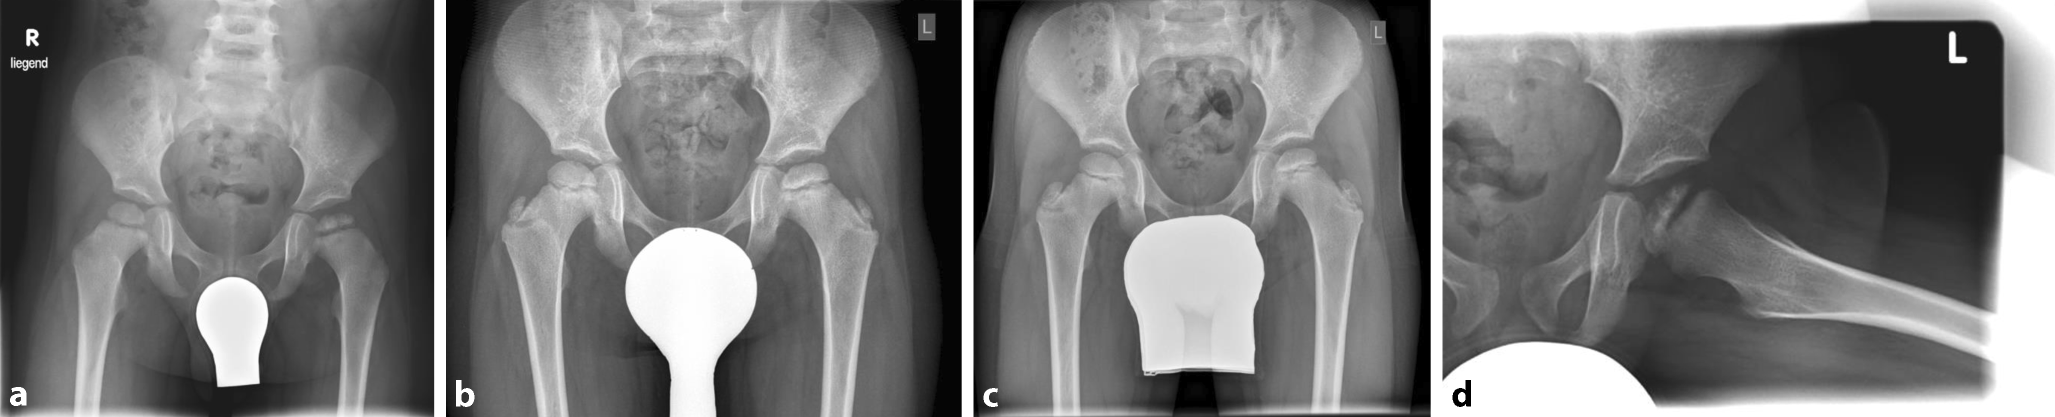

Abb. 4

Krankheitsverlauf bei operativer Containment-Therapie mithilfe einer rechtsseitigen proximalen varisierend-derotierenden Femurosteotomie. Patientenalter: a 6 Jahre 4 Monate, b 6 Jahre 5 Monate, c 6 Jahre 9 Monate, d 7 Jahre 6 Monate, e 8 Jahre 2 Monate, f 9 Jahre 8 Monate, g 11 Jahre, h 14 Jahre, i 17 Jahre

• eine proximale Femur-Varus-Osteotomie (Abb. 4), die möglicherweise auch eine Verminderung der Fragmentation bewirkt [34] oder